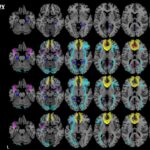

Microstructural changes in the white matter can be helpful for early detection and characterization of different subtypes of dementia, including Alzheimer’s disease. Article: Exploring quantitative group-wise differentiation of Alzheimer’s disease and behavioural...